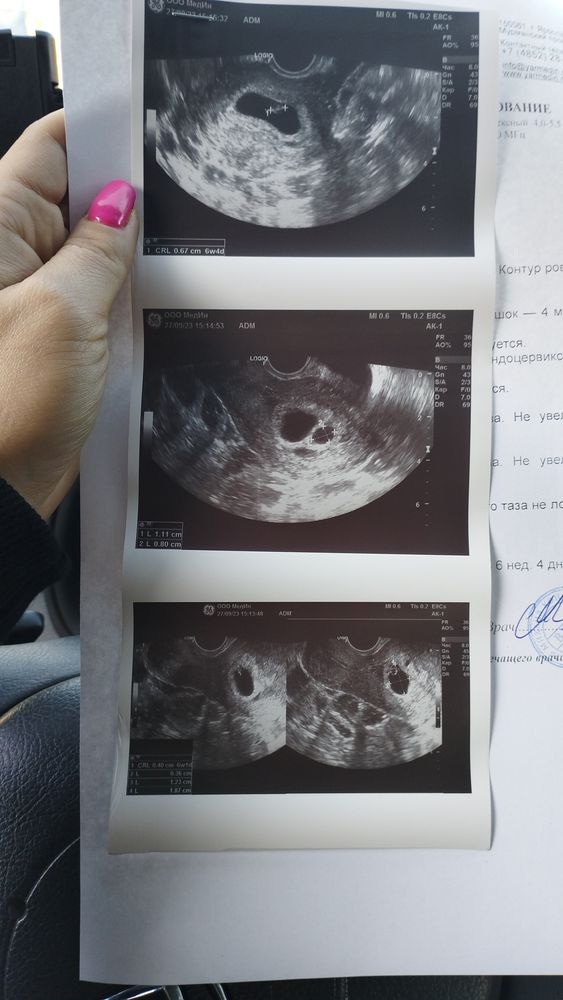

Внутриутробное развитие двойни/тройниЗдравствуйте. Подскажите пожалуйста🙏нашли 2 плодных яйца. В 1пя-эмбрион 6,7мм сердцебиение есть свд 19мм.срок поставили 6и4 дня. во 2пя эмбрион не лоцируется свд 11мм.возможно ли что еще чуть позже ребенок появится во 2пя или надежды уже нет?

Вот фото узи